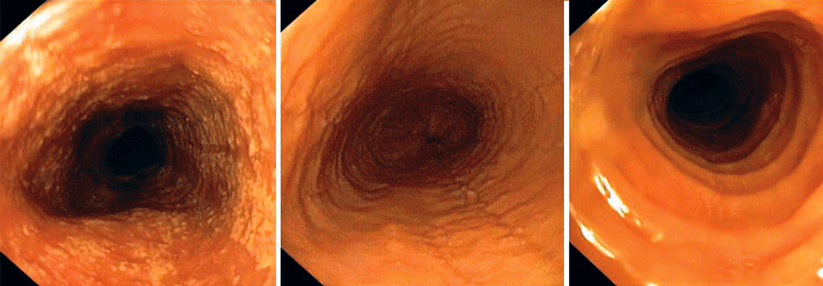

Die Diagnostik einer Dysphagie beruht auf einer sorgfältigen Anamnese (s. Kasten), der klinischen Untersuchung der beteiligten Organe (Mundmotorik, Schleimhautbefund, Auslösen des Schluck- und Würgreflexes) und der für den Schluckvorgang wichtigen Hirnnerven (Nn. facialis, hypoglossus, glossopharyngeus, vagus). Eine transnasale video­fiberendoskopische Beurteilung des gesamten Aktes schließt sich an, denn mit dieser nicht-invasiven Methode lassen sich Bewegungsstörungen, Tonusänderungen und weitere Auffälligkeiten erfassen. Die Bildgebung hat bei Stenosen oder Zenker-Divertikeln ihren Platz.